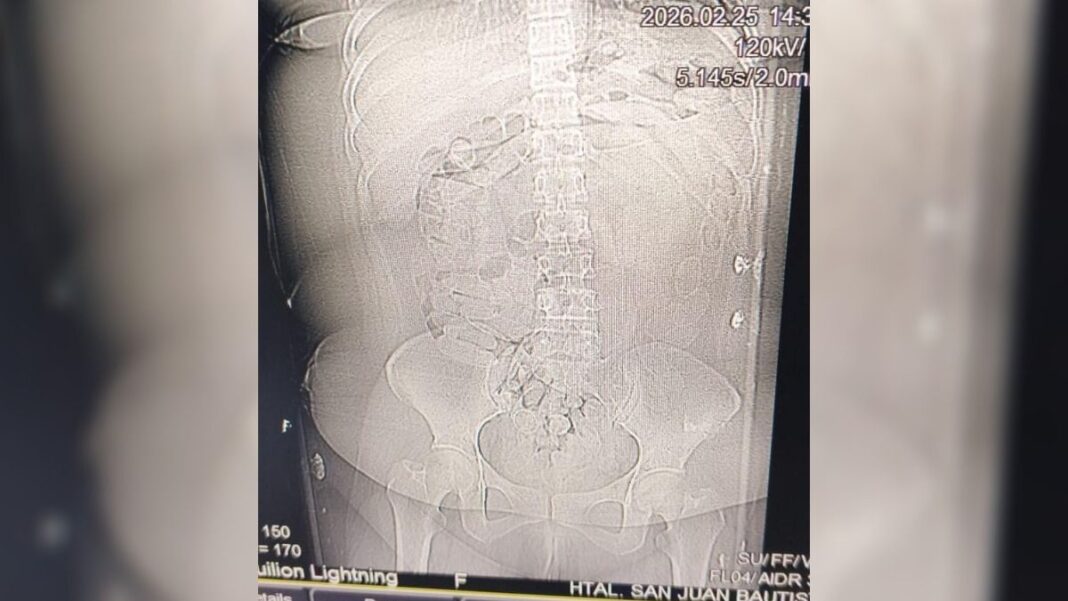

Tras los estudios correspondientes, se constató la presencia de cuerpos extraños en la zona abdominal y en la cavidad genital. Como resultado del seguimiento médico, se confirmó la evacuación de 90 cápsulas.

image

La sustancia contenida en los envoltorios era de color blancuzco y, al ser sometida a la prueba de campo Narcotest, arrojó resultado positivo para cocaína, con un peso total de 1 kilo 069 gramos.